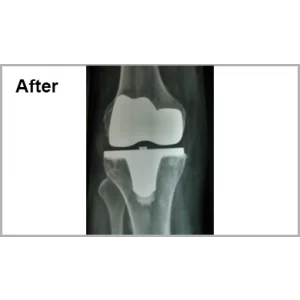

Male aged 60 years had significant difficulty in walking and pain in his right knee. He was operated inform of lumber fusion and right total knee replacement. At present, he absolutely pain free and walking without any support since more than 7 years.